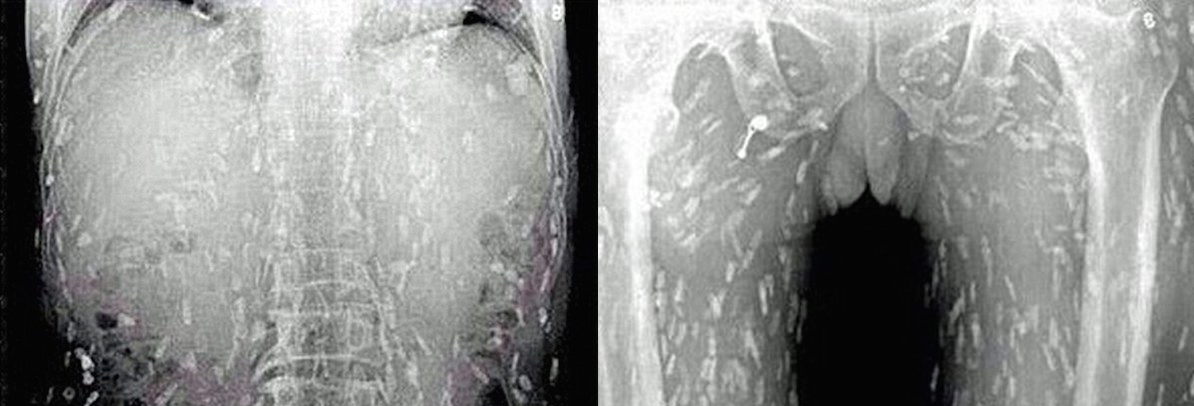

Tapeworms Found Inside Man’s Body After Eating Bad Sushi